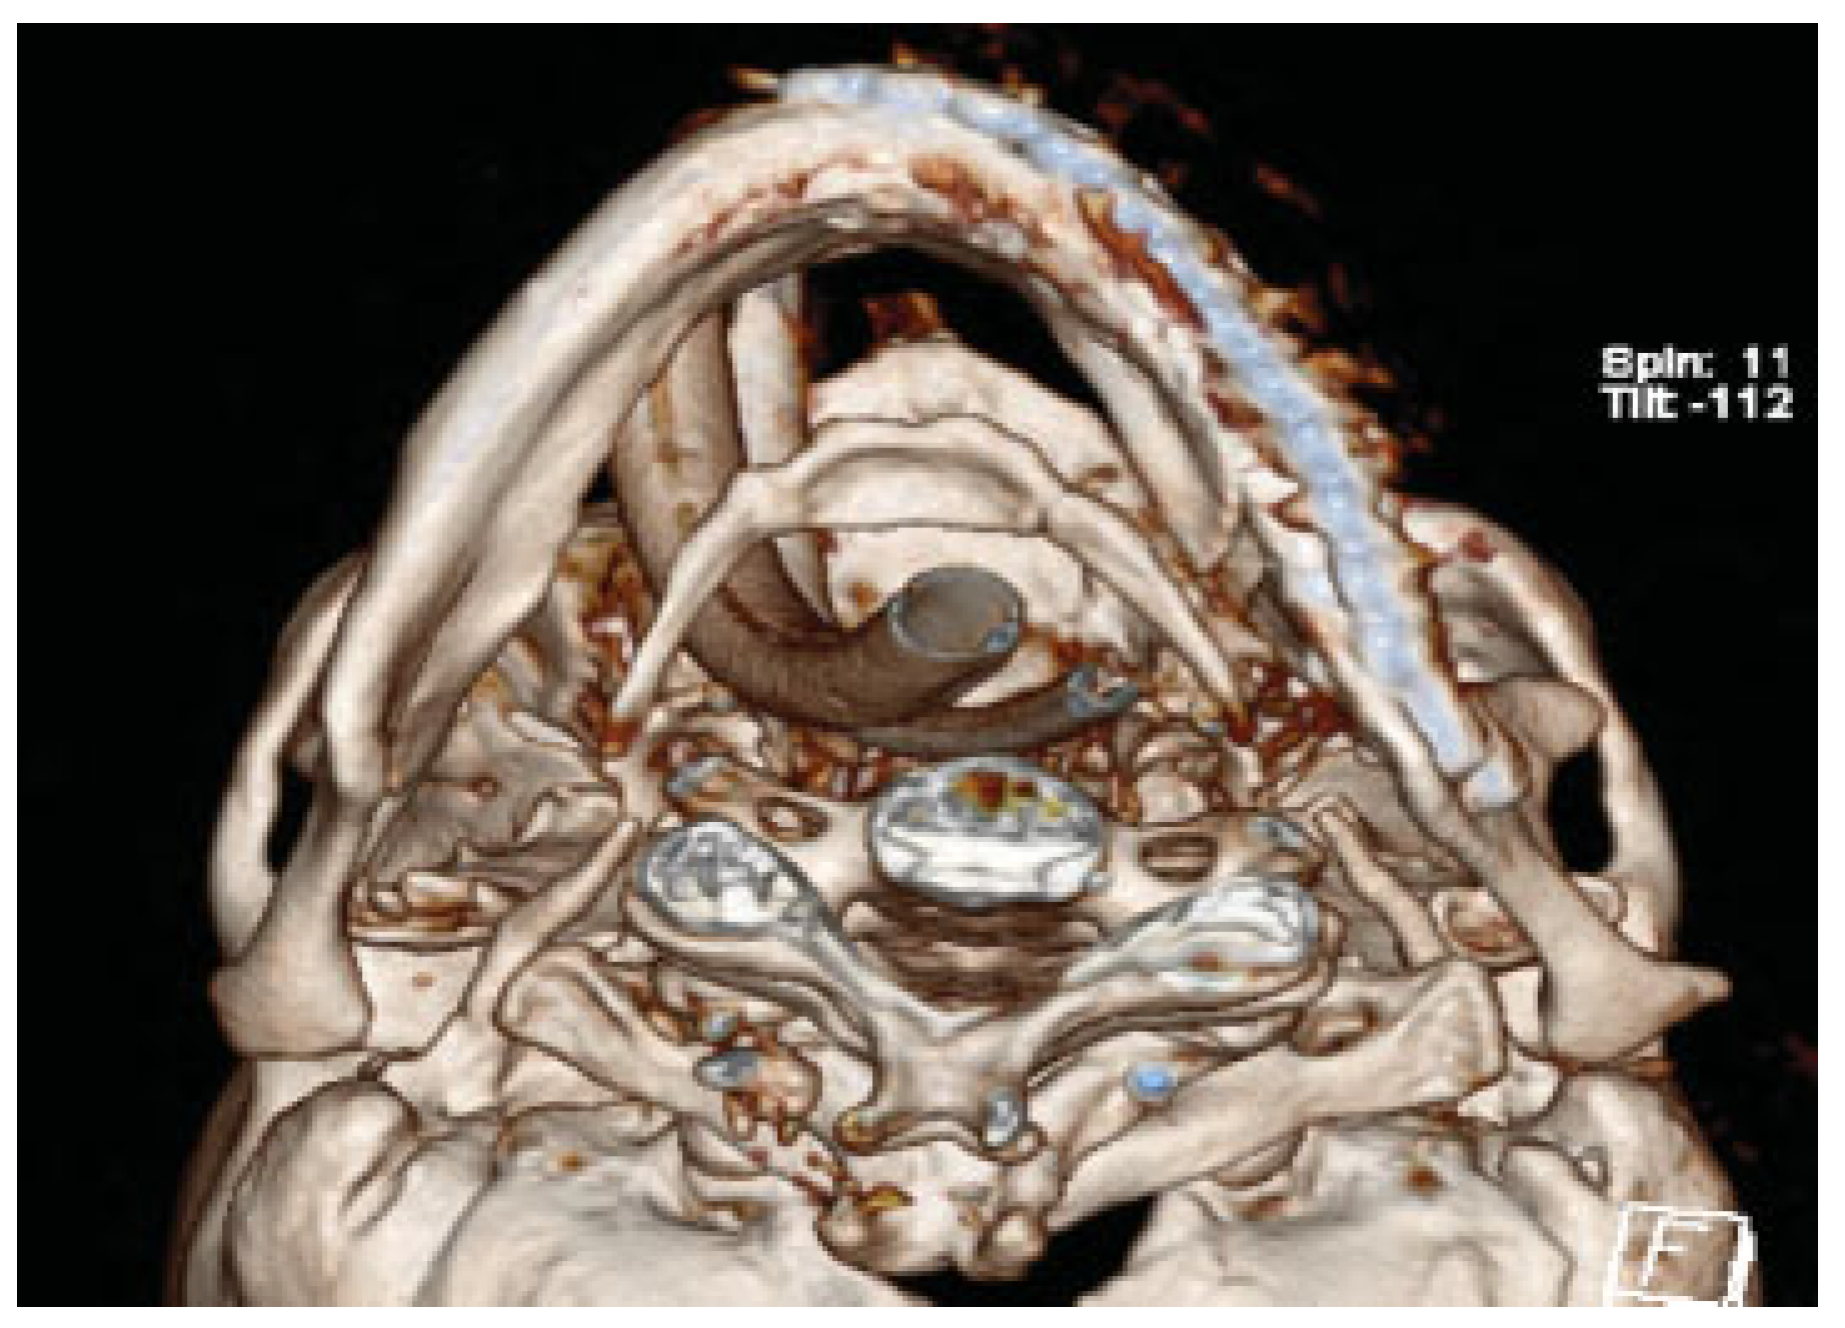

A 72-year-old male patient involved in a roll over tractor accident presented to an outside hospital where he was intubated. Injuries included right upper extremity degloving injury and multiple unstable cervical spine injuries of anterior and posterior columns requiring fusion of C5–T1. It was elected by the spine service not to fuse C2 to allow him rotation of his neck. A CT scan revealed bilateral intracapsular condylar head fractures, a left comminuted mandible fracture, and complex nasal fracture (Figure 1a–c). Additionally, he had a transverse body fracture of C2 and C5 through T1. The patient was transferred to the University of Kentucky for further management.

Figure 1. (a) 3D preoperative CT reconstruction of the injury from a three-fourths view. Note the intracapsular head fracture on the left. (b) Submental vertex view showing displacement and comminution. (c) Axial CT showing comminution. As the maxillary fracture was minimally displaced, the authors believed that any discrepancies would be resolved with an eventual prosthesis.